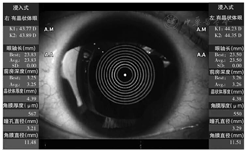

目前,应用于白内障检查和IOL预测方面的SS-OCT生物测量仪设备主要是IOLMaster 700和OA-2000。IOLMaster 700扫频光源波长为1 055 nm,扫描深度为44 mm,眼前节和视网膜扫描宽度分别为6 mm和1 mm,组织分辨率为22 μm[10];测量时发出的激光以2 000次/s的速度从6个不同方向(0°、30°、60°、90°、120°、150°)进行平面扫描,实现了从角膜顶点至视网膜的全眼轴长可视化测量,还可以截取视网膜的OCT图像以确认固视。OA-2000扫频光源波长为1 060 nm[11],扫描速度为1 000次/s,也具有较强的穿透性和较高的信噪比。IOLMaster 700角膜曲率的测量采用远心光学技术保证测量位置不受操作时对焦准确性的影响,3环(直径1.5、2.5和3.5 mm)18点的测量模式进一步提高了测量准确性和一致性(图1)。OA-2000在SS-OCT基础上,采用Placio盘角膜地形图技术测量角膜曲率,可获得直径2.5 mm、3.0 mm的角膜曲率;除了测量一系列眼部生物参数,如AL、K1和K2、ACD、LT、WTW、瞳孔直径(pupil distance,PD)和中央角膜厚度(central corneal thickness,CCT)外,其还可以绘制角膜地形图,具有角膜地形图仪的功能(图2)。在内置IOL屈光度计算公式方面,IOLMaster 700在SRK-T、Hoffer Q、Holladay2、Haigis以及Haigis-L公式基础上,新增了Haigis-T公式,即将内置Barrett公式组(Barrett Universal Ⅱ、Barrett Toric、Barrett True-K)。OA-2000上述公式均有内置。